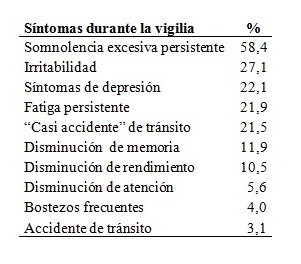

Tabla 4: Síntomas durante la vigilia

Tabla 4. Frecuencia de pacientes con síntomas relatados durante la vigilia (n=447).

El ronquido y la somnolencia diurna excesiva persistente fueron los síntomas más frecuentes. La escala de somnolencia de Epworth tuvo un puntaje promedio de 10,4 ± 6,2. Utilizando el límite de corte habitual de 10 puntos, la sensibilidad para predecir más de 5 apneas por hora de sueño fue de 84,3% y la especificidad 16,4%. El 48,6% de los pacientes tuvieron un puntaje igual o mayor a 10, que indica somnolencia moderada a severa. No se encontró correlación entre el puntaje y los índices de severidad de las apneas del sueño: índice de apneas-hipopneas por hora (IAH), Índice de desaturación de oxígeno (IDO) e Índice de despertares (Idesp).